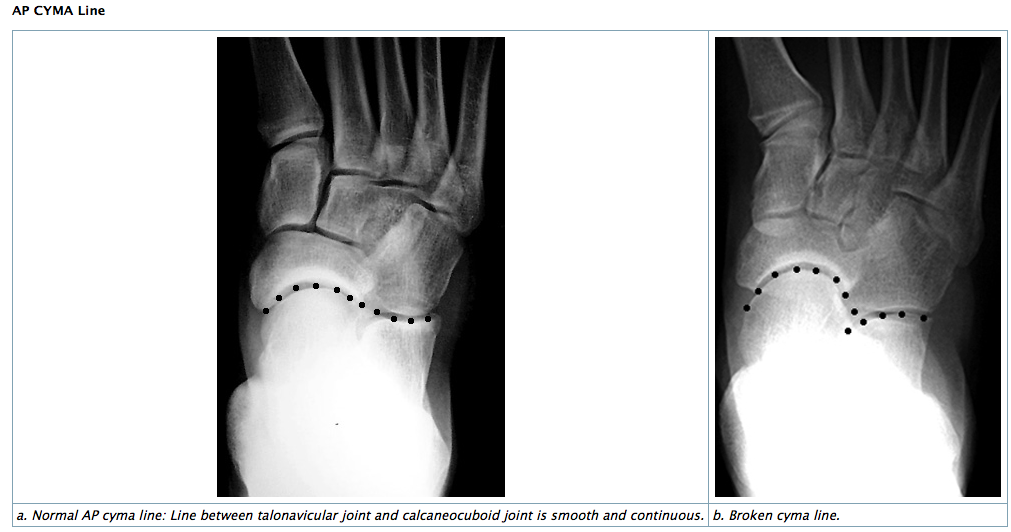

• AP & Lateral: CYMA line